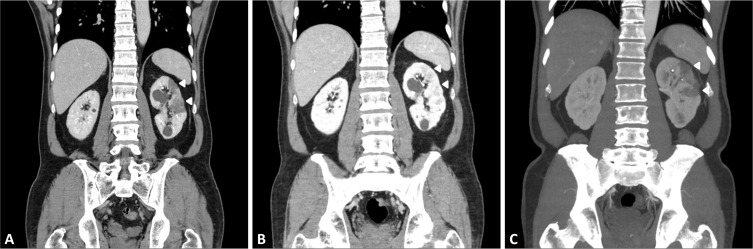

虽然肾梗塞(RI)并不是一种罕见疾病,但其结果却没有得到很好的记录。此外,RI 的一过性缓解和复发也没有通过影像学检查记录下来。我们报告了一例特发性 RI 病例,通过连续计算机断层扫描(CT)显示,该病在一过性缓解后的短时间内又复发了。一名 53 岁的男子被诊断为 RI,转入急诊室。在当地医院进行的腹部 CT 扫描显示左肾有节段性楔形灌注缺损,左肾动脉前段分支有局灶性血栓性充盈缺损。由于他的左侧腹痛有所改善,在首次 CT 扫描 6 小时后再次进行了 CT 扫描。复查 CT 显示,肾动脉内的血栓仍然存在,但灌注缺损已自行消退。我们开始使用非分数肝素进行抗凝治疗。住院第六天,左侧腹痛再次出现,促使我们再次进行了 CT 扫描。后续的 CT 扫描证实,RI 在之前的同一部位复发。我们继续进行抗凝治疗,并改用华法林。治疗后,他的症状有所改善,并已出院。正如我们的病例所示,RI 可在任何时候复发,即使在自发缓解后也是如此。因此,密切监测 RI 缓解的患者是否再次出现症状至关重要,即使在短时间内也应重复进行放射学评估。

Although renal infarction (RI) is not a rare disease, its outcomes have not been well-documented. Furthermore, transient resolution and recurrence of RI have not been captured through imaging. We report a case of idiopathic RI that recurred within a short period following transient resolution, as demonstrated by serial computed tomography (CT). A 53-year-old man diagnosed with RI was transferred to the emergency room. An abdominal CT scan at the local hospital revealed a segmental wedge-shaped perfusion defect in the left kidney and a focal thrombotic filling defect in the anterior segmental branch of the left renal artery. Since his left flank pain improved, another CT scan was performed again 6 hours after the initial CT scan. A repeat CT scan showed that the thrombus in the renal artery remained, but the perfusion defect had spontaneously resolved. We initiated anticoagulant therapy using unfractionated heparin. On the sixth day of hospitalization, the left flank pain recurred, prompting another CT scan. The follow-up CT scan confirmed that RI had recurred in the same area as before. We continued anticoagulant therapy and switched to warfarin. After treatment, his symptoms improved, and he was discharged. RI can recur at any time, even after it has spontaneously resolved, as evidenced by our case. Therefore, it is crucial to closely monitor patients who experience resolution of RI for any recurrence of symptoms, and repeat radiological evaluation should be performed even within a short period.